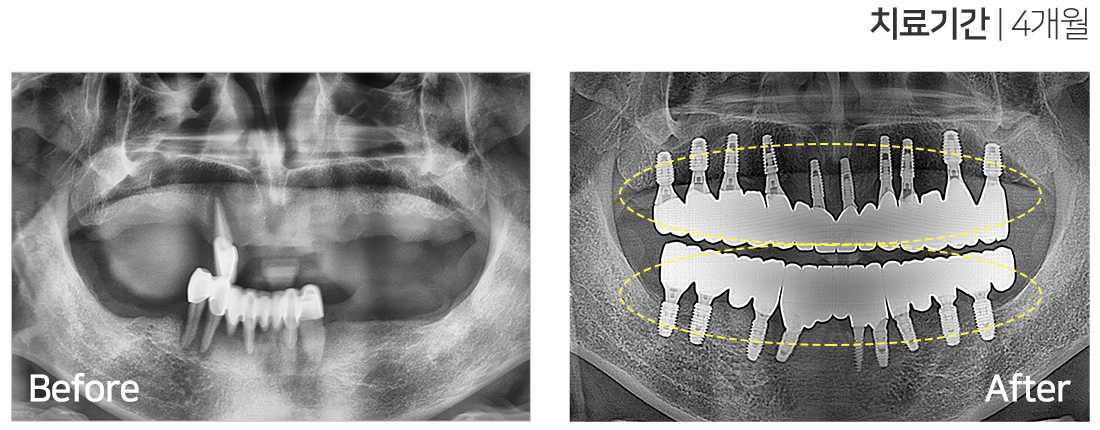

임플란트 시술 사례

IMPLANT TREATMENT CASES

※ 전신질환 및 관리 능력에 따라 임플란트 주위염 등의 부작용이 있을 수 있습니다.